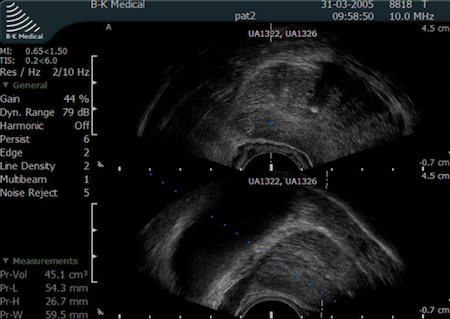

Fot. Obraz stercza w transrektalnym USG.